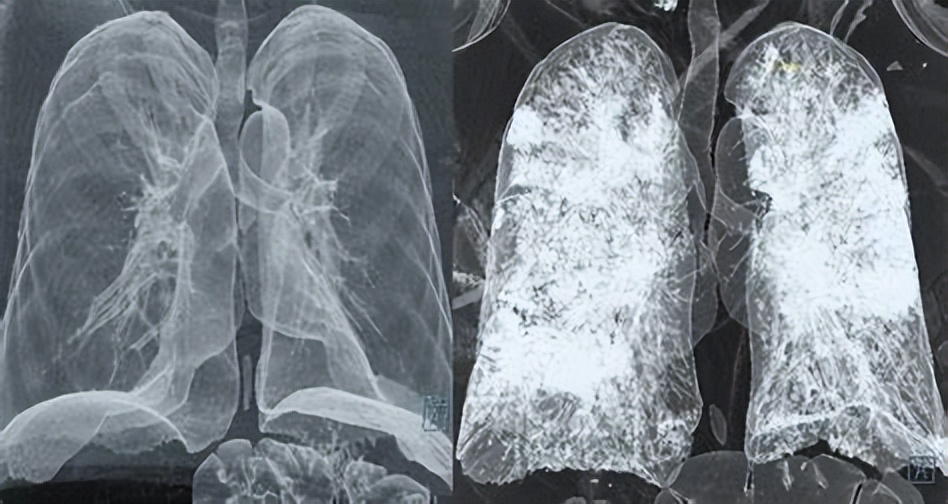

痰液真正的危害在于,咳不出,大量沉积在呼吸道内,导致呼吸道的堵塞,加重感染,并影响氧气在肺内与血液的交换,导致身体缺氧。

这主要见于严重感染,呼吸道分泌物急剧增加,而感染又造成呼吸道自净机制的破坏,比如,重症和危重症新冠肺炎;慢性阻塞性肺病,特别是高龄老年人肺病发作合并急性感染等状况。